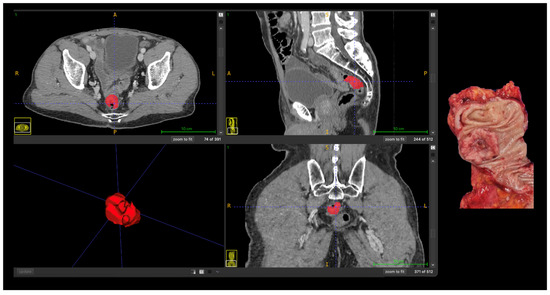

All segmentations were performed following a standardized institutional protocol by a single radiologist, using multiplanar visualization in ITK-SNAP software (version 3.8; www.itksnap.org) to ensure anatomical consistency. In cases with ambiguous tumor margins or complex anatomy, segmentations were supervised and reviewed by a senior abdominal radiologist to ensure anatomical accuracy. The region of interest (ROI) was delineated along the tumor boundary on three consecutive axial slices that best represented the lesion. Areas of intraluminal air, necrosis, vascular structures, and pericolic fat were carefully excluded from the contours (Figure 1).

Manual segmentation of colorectal tumor (Patient 18) on portal venous phase CT and corresponding surgical specimen. The region of interest (ROI) was manually delineated (in red) on three consecutive slices using ITK-SNAP software, excluding intraluminal air, necrosis, vessels, and pericolic fat. Abbreviations: ROI, region of interest; CT, computed tomography; A, anterior; P, posterior; R, right; L, left, S, superior; I, inferior.

Representative case illustrating the correspondence between radiomics-based tumor segmentation on contrast-enhanced CT and the corresponding pathological anatomy are shown in Figure 3.

Correlation between radiomics-based tumor segmentation on contrast-enhanced CT and pathological anatomy in advanced (T4) colon cancer. Axial, coronal, and sagittal CT images with manual tumor segmentation (red); Three-dimensional rendering of the segmented tumor; Corresponding gross surgical specimen. Abbreviations: A, anterior; P, posterior; R, right; L, left, S, superior; I, inferior.